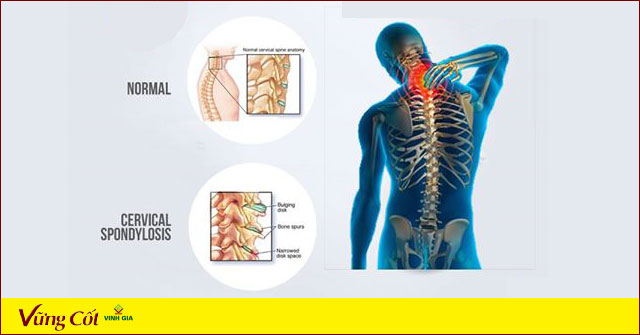

Thoái hóa đốt sống cổ là tình trạng bệnh lý do thoái hóa của các xương, sụn, các cơ dây chằng, các phần mềm và bao hoạt dịch của đốt sống. Bệnh thoái hóa đốt sống cổ thường có các biểu hiện sớm thường gặp là:

- Thoái hoá đốt sống cổ làm cột sống và các khớp có thể bị biến dạng, sưng và đau, gây hạn chế vận động. Bệnh gây nên các hội chứng thần kinh như đau dây thần kinh chẩm, hội chứng vai gáy và cánh tay. Nó còn gây các hội chứng tuần hoàn do làm hẹp lỗ ngang, khiến cho động mạch đốt sống bị hẹp, gây ra rối loạn tuần hoàn não làm cho bệnh nhân thấy ù tai, mờ mắt, chóng mặt, mất ngủ, …

- Thoái hoá đốt sống cổ còn có thể gây bại liệt một hoặc hai tay, gây hội chứng chèn ép tủy, cổ, rối loạn cảm giác tứ chi, chèn ép rễ thần kinh, tủy hoặc cả hai hoặc gây rối loạn thần kinh thực vật. Các biến chứng có thể gặp của bệnh bao gồm đau dọc từ cổ xuống vai và cánh tay một hoặc cả hai bên, đau đầu, chóng mặt; khi có chèn ép tủy, thần kinh sẽ gây yếu, đau tứ chi, đi lại khó khăn hoặc liệt không vận động được.

- Đốt sống cổ bị thoái hóa để lâu không điều trị sẽ dẫn đến các nguy cơ như hạn chế khả năng cung cấp máu lên não của cơ thể, rất nguy hiểm.

Như vậy, bên cạnh sự đau đớn, thoái hóa đốt sống cổ còn gây teo cơ, nguy cơ thoát vị do động tác sai, bại liệt, thậm chí liệt tứ chi dẫn đến nhiễm trùng phổi, tiết niệu và tử vong.